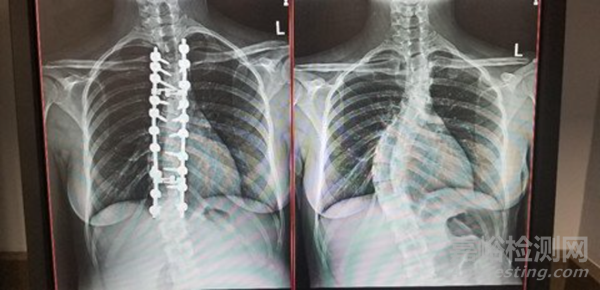

標(biāo)準(zhǔn)融合手術(shù)通常涉及在治療節(jié)段放置椎弓根螺釘和短桿以保持脊柱穩(wěn)定性。

這些椎弓根螺釘?shù)哪康氖窃谙噜徸倒侵g形成堅(jiān)固的橋,作為一種穩(wěn)定形式。放置椎弓根螺釘結(jié)構(gòu)需要至少 4-6 個(gè)雙側(cè)切口,并且可能因定位不正確而產(chǎn)生相關(guān)并發(fā)癥。